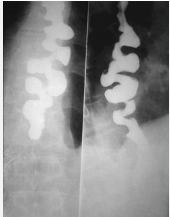

Divertículos

• Zenker: Hipofaringe póstero-lateral

• Traction: Médio esôfago (fibrose)

• Epifrênico: Próximo ao diafragma

Divertículo de Zenker

Divertículo de Zenker - hipofaringe posterior